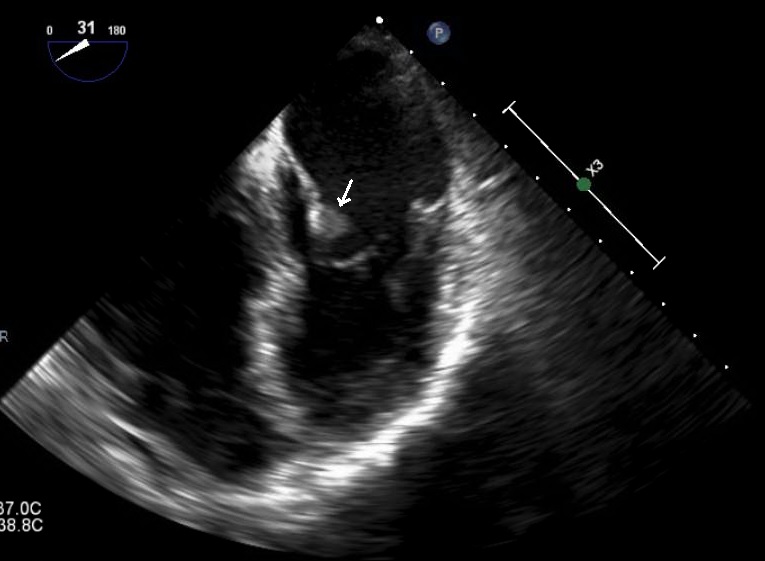

Case Presentation: A 52 year-old man was hospitalized for hypoxia one month after surgery for ruptured appendicitis. He also reported abdominal pain and steatorrhea along with a 50 pound weight loss in five months. On exam he was anicteric but cachectic. CT pulmonary angiogram on admission revealed peripheral-based pulmonary lesions concerning for septic emboli and incidental hepatic lesions. A follow-up CT of the liver revealed multiple small liver lesions and a possible hypo-attenuating pancreatic lesion. His Cancer Antigen 19-9 was 777 U/ml and fecal elastase was undetectable. Our main concern was for pancreatic adenocarcinoma but we considered septic emboli in our differential given his recent ruptured appendicitis. A CT-guided liver biopsy was non-diagnostic with negative cultures of the tissue as well as the blood. Endoscopic ultrasound failed to confirm the patient’s liver lesions. Patient was discharged and readmitted with worsening symptoms and CT findings. Transesophageal echocardiogram revealed thickening and probable small vegetations of the mitral and aortic valves suggestive of non-bacterial thrombotic endocarditis (NBTE). MRI of the abdomen showed a 9×6 mm lesion in the pancreatic head. A repeat liver biopsy resulted with moderately differentiated mucin-producing pancreatic adenocarcinoma. Patient’s repeat CA-19-9 had increased to 6008 U/ml one month after his initial presentation. The patient was diagnosed with metastatic pancreatic adenocarcinoma with systemic emboli from NBTE. He elected to pursue hospice services at home and subsequently discharged from the hospital.

Discussion: When hematogenous spread of infection is on the differential with malignancy, one must be cognizant of NBTE as a cause of systemic embolization. Up to 80% NBTE causes are due to advanced malignancy with lupus coming in a distant second. It is estimated that 10% of patients with mucin-producing adenocarcinoma have NBTE. This patient’s presentation favored pancreatic adenocarcinoma considering his profound weight loss, steatorrhea and elevated CA-19-9. The variation in the appearance of his hepatic and pancreatic lesions on different imaging modalities and the negative initial liver biopsy delayed the diagnosis as extensive infectious workup for septic emboli was pursued. The prognosis of NBTE is poor due to its association with advanced malignancy. As illustrated by this patient’s case, mortality in pancreatic adenocarcinoma approaches 80% in the first year of diagnosis due to its late presentation.

Conclusions: Although septic emboli and infective endocarditis are more common in the general patient population, NBTE with resultant embolic events should be considered in any patient with a concern for advanced malignancy. In this case, MRI was superior for soft tissue discrimination over CT and ultrasound. A non-diagnostic biopsy in the setting of high clinical suspicion for malignancy is likely to represent sampling error, especially in cases of NBTE.